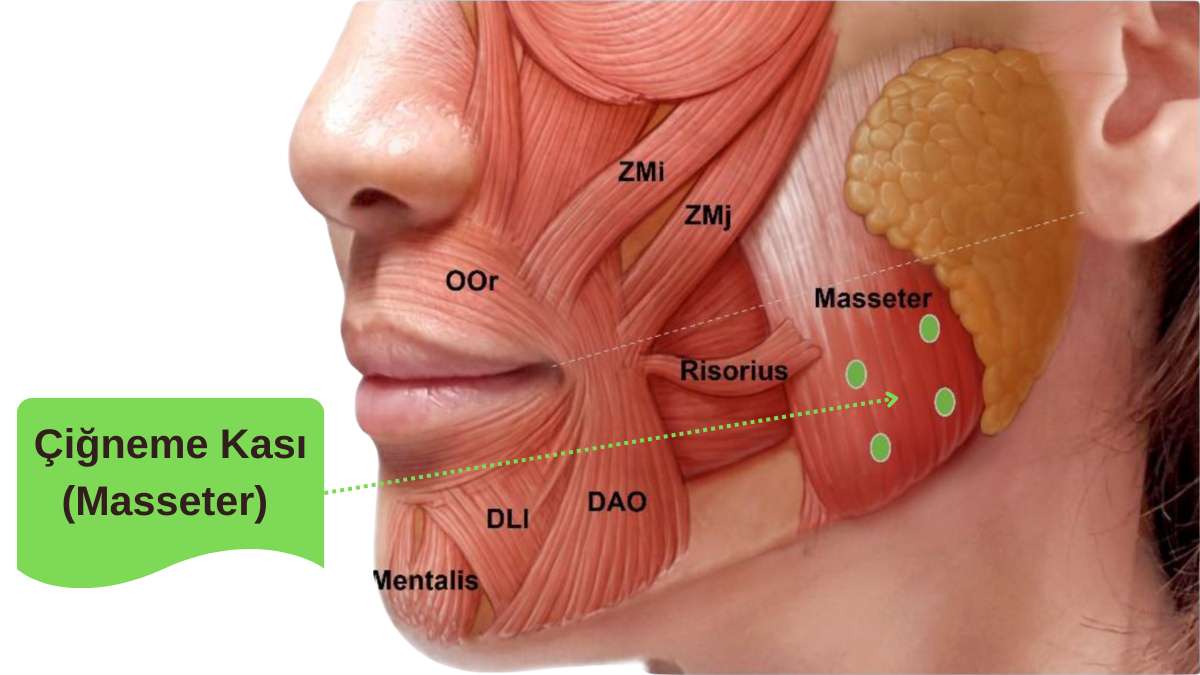

“Sabah yorgun uyanıyorum, şakaklarım ağrıyor, dişlerim sızlıyor” diyen hastalarda sık karşılaştığımız tablo bruksizmdir. Gece diş sıkma; çoğu zaman fark edilmeden, çene kaslarını (özellikle masseter ve temporal kasları) uzun süre yüksek yük altında bırakır. Sonuçta kas ağrısı, baş ağrısı, dişlerde aşınma ve TME’de zorlanma görülebilir. Bu nedenle diş sıkma tedavisi, yalnızca “dişi korumak” değil; eklem ve kas dengesini de korumak açısından önemlidir.

Diş sıkma (bruksizm) problemine ve çene ağrılarına neden olabilen aşırı aktif Masseter (çiğneme) kası.

Bu başlıkta sık sorulan uygulamalardan biri masseter botoksudur. Uygun hastalarda amaç, aşırı çalışan kasın aktivitesini azaltıp kas- eklem yükünü dengelemeye yardımcı olmaktır. Bazı kişilerde çiğneme kası hacmi belirgin olduğunda yüz alt bölümünde incelme gibi estetik bir değişim de gözlenebilir; ancak bu, tedavinin temel hedefi değil, ikincil bir etki olarak değerlendirilmelidir. Hangi yöntemin uygun olduğuna; muayene bulguları, sıkmanın şiddeti, dişlerdeki aşınma düzeyi ve eklem bulguları birlikte değerlendirilerek karar verilir.

Evet, çene eklemi rahatsızlıklarının en yaygın nedenlerinden biri “Bruksizm” yani diş sıkma ve gıcırdatma alışkanlığıdır. Genellikle strese bağlı gelişen bu durumda, çene kasları (masseter) gece boyunca ekleme aşırı yük bindirir. Bu sürekli baskı, zamanla eklem diskinin yapısını bozabilir ve ağrılı spazmlara yol açabilir. Bu nedenle tedavinin başarısı için sadece eklemin değil, diş sıkma alışkanlığının da (plak veya botoks uygulamaları ile) kontrol altına alınması gerekir.